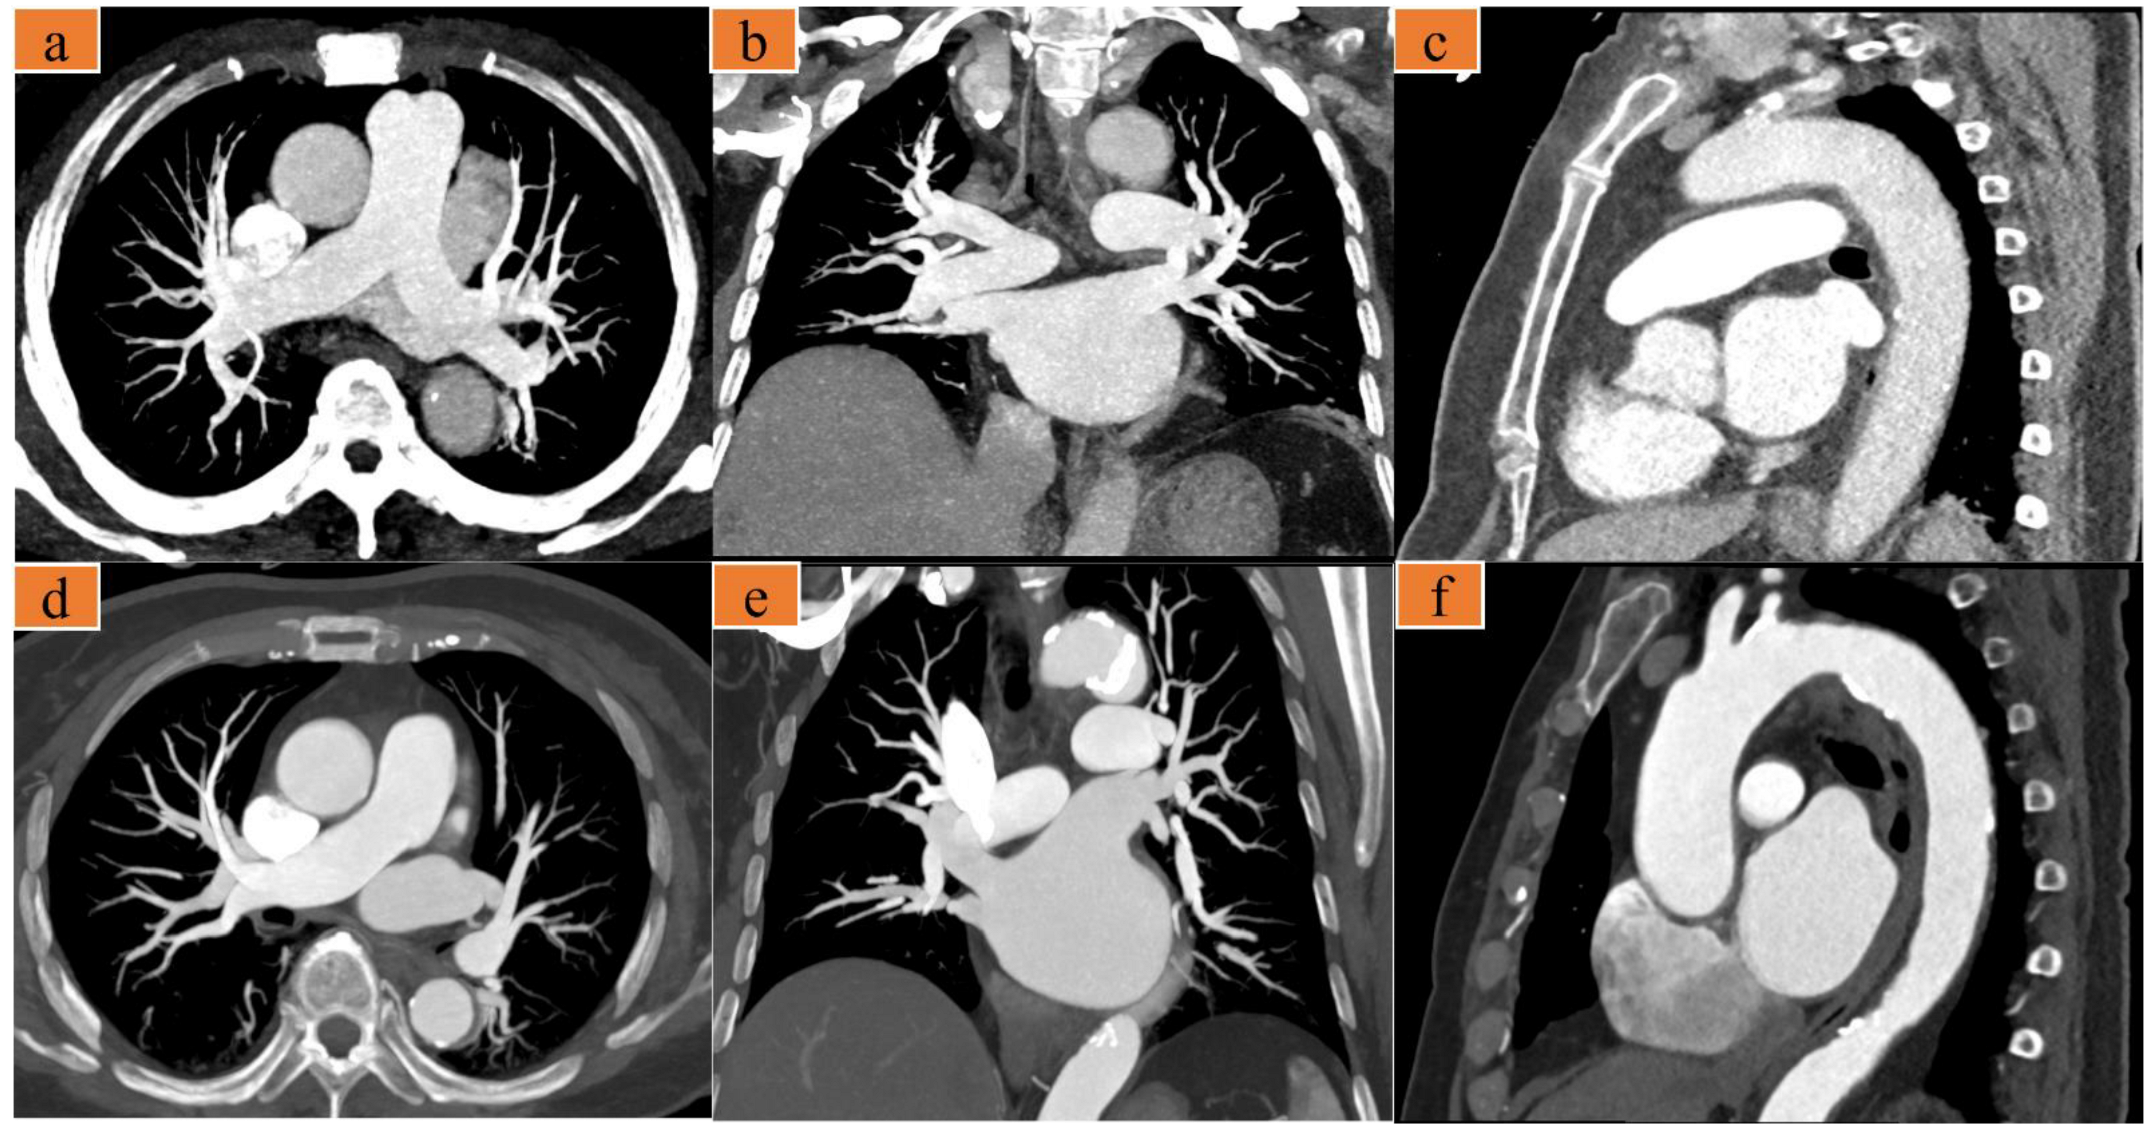

2.3. Image Reconstruction and Evaluation